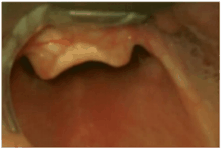

Após adequado posicionamento, sedação e bloqueio neuromuscular e laringoscopia por operador experiente, obteve-se a seguinte imagem à laringoscopia:

A classificação de Cormack da via aérea do doente é